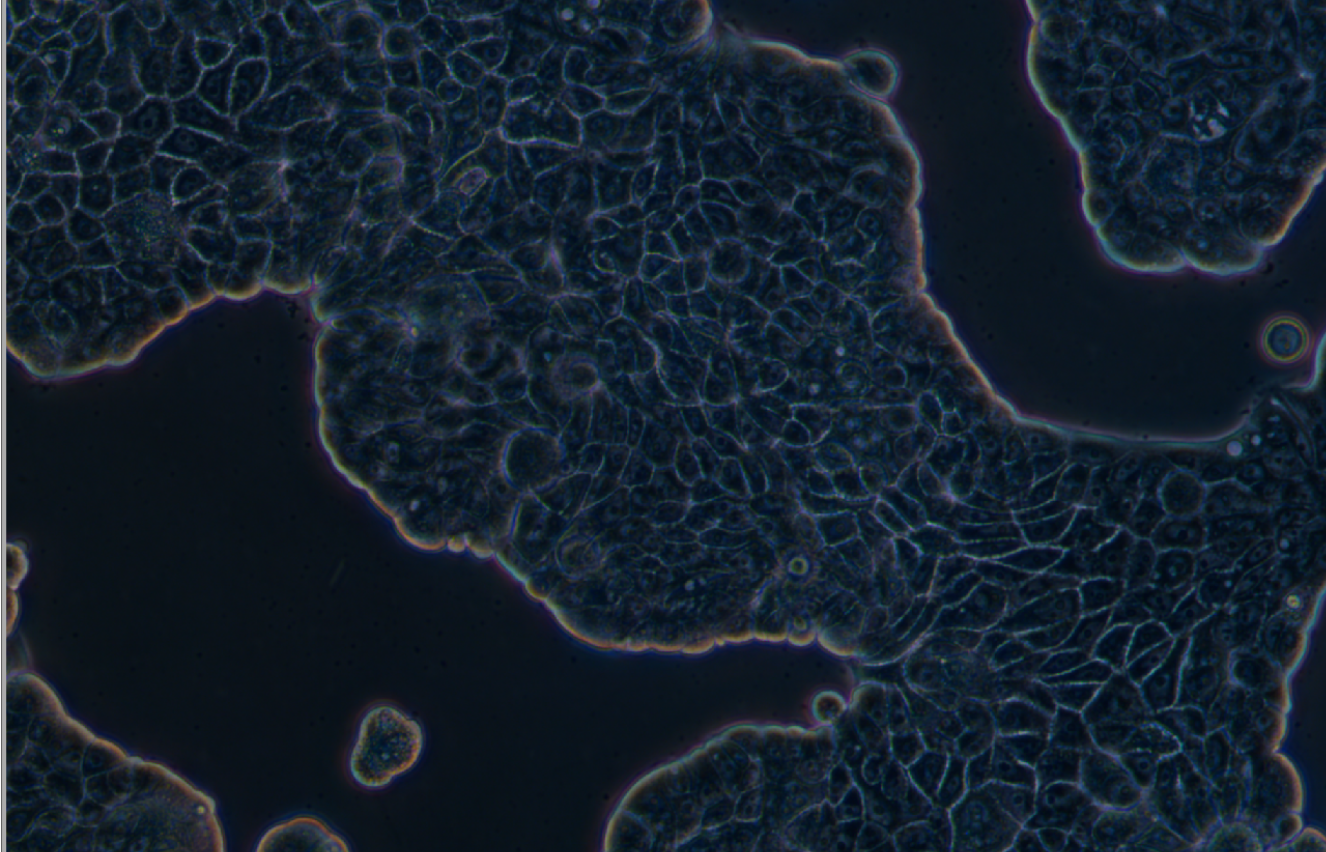

形態 |

上皮細胞樣 |

生長特征 |

貼壁生長 |